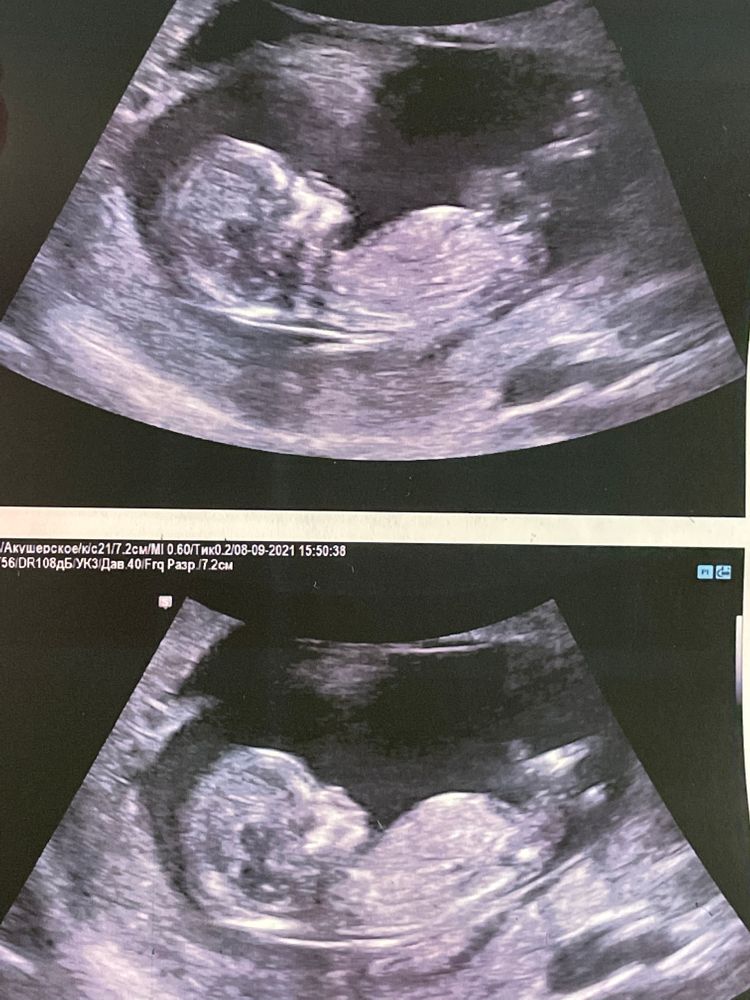

Все хорошо, малышок наш 62мм уже. Активный, ручками, ножками дрыгал. Спинкой повернулся, позвоночник, ребрышки, лопатки, такое все миленькое 😭😭😭❤️❤️❤️

Все хорошо, малышок наш 62мм уже. Активный, ручками, ножками дрыгал. Спинкой повернулся, позвоночник, ребрышки, лопатки, такое все миленькое 😭😭😭❤️❤️❤️

Очень похожа на неё, очень аккуратное строение черепа и половой бугорок, если правильно рассмотрела указывают на то, что эта девчуся 💗! Я короче говоря держу кулачки за это и от всего сердца желаю здоровую сестричку вашей доченьке 💞😻🤗

Когда я к нему пришла уже знала пол, но ему не говорила. Он подтвердил ) 13недель было

Маруся, я на мониторе сама увидела)))) Он говорит, пол говорить? Я - девочка? Он - да.

Те молодец, его словам явно можно верить. А я не понимаю как все видят что-то на таких фотках. Но ставлю на девочку.